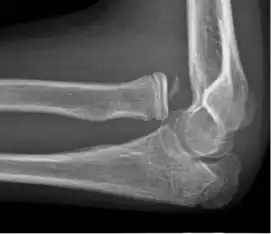

The elbow undergoes dynamic development of ossification centers through infancy and adolescence, with the order of both the appearance and fusion of the apophyseal growth centers being crucial in assessment of the pediatric elbow on radiograph, in order to distinguish a traumatic fracture or apophyseal separation from normal development. The order of appearance can be understood by the mnemonic CRITOE, referring to the capitellum, radial head, internal epicondyle, trochlea, olecranon, and external epicondyle at ages 1, 3, 5, 7, 9 and 11 years. These apophyseal centers then fuse during adolescence, with the internal epicondyle and olecranon fusing last. The ages of fusion are more variable than ossification, but normally occur at 13, 15, 17, 13, 16 and 13 years, respectively.[16] In addition, the presence of a joint effusion can be inferenced by the presence of the fat pad sign, a structure that is normally physiologically present, but pathologic when elevated by fluid, and always pathologic when posterior.[17]

Fractures

There are three bones at the elbow joint, and any combination of these bones may be involved in a fracture of the elbow. Patients who are able to fully extend their arm at the elbow are unlikely to have a fracture (98% certainty) and an X-ray is not required as long as an olecranon fracture is ruled out.[27] Acute fractures may not be easily visible on X-ray.[28]